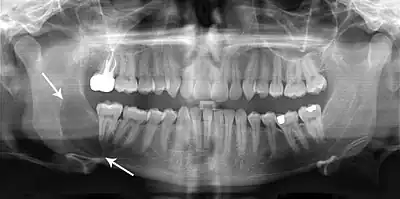

Radiograficamente, exibem uma área radiolúcida, apresenta-se como uma rarefação óssea uni ou multiocular, com bordas escleróticas frequentemente bem definidas, podendo ou não estar associadas com um dente impactado e, geralmente essa lesão possui uma discreta predileção de crescimento anteroposterior. Geralmente são analisadas radiografias panorâmicas e tomografia computadorizada, pois a radiografia panorâmica fornece, com qualidade, a extensão da lesão cística e sua relação com estruturas adjacentes, no entanto a tomografia computadorizada tem indicação indispensável para o planejamento cirúrgico, apresentando detalhes preciosos sobre a expansão da lesão, a localização de dentes envolvidos e a topografia de suas margens (espessura e perfuração das corticais ósseas)do que as radiografias convencionais. O uso racional indica tomografias computadorizadas somente para lesões extensas. O CO, pode muitas vezes ser confundido com cisto dentígero por em 44% dos casos está associado com dentes inclusos, porém observa-se também menos comum que o radicular, reabsorção óssea das raízes dos dentes adjacentes, normalmente ocorre um deslocamento do dente e não reabsorção da raiz. É importante salientar que apenas o diagnóstico histopatológico é determinante.